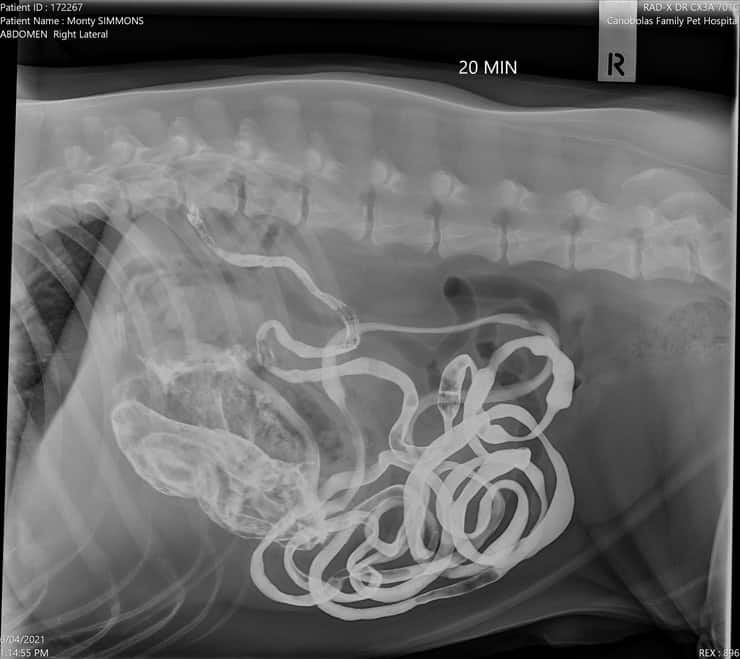

Per determinare la causa del suo malessere i veterinari decisero di sottoporlo a ben due cicli di raggi X per assicurarsi che non si trattasse di una ostruzione intestinale, di un’ulcera o peggio di svariati tumori diffusi.

Secondo quanto raccontato sulla pagina Facebook infatti :“Le immagini di contrasto mostravano che il suo intestino funzionava normalmente, lo stomaco si svuotava, ma c’era anche qualcosa che non andava bene nello stomaco”.

“La mattina dopo il ricovero, Monty si è sottoposto a un intervento chirurgico dove non abbiamo trovato uno, non due, non tre ma quattro calzini nello stomaco”.

A quanto pare infatti i proprietari del cane avevano subito pensato a un gravissimo tumore, mentre a causare l‘irritazione cronica e il sanguinamento nello stomaco che portava il cane all’anemia erano 4 calzini ingeriti dal cane.